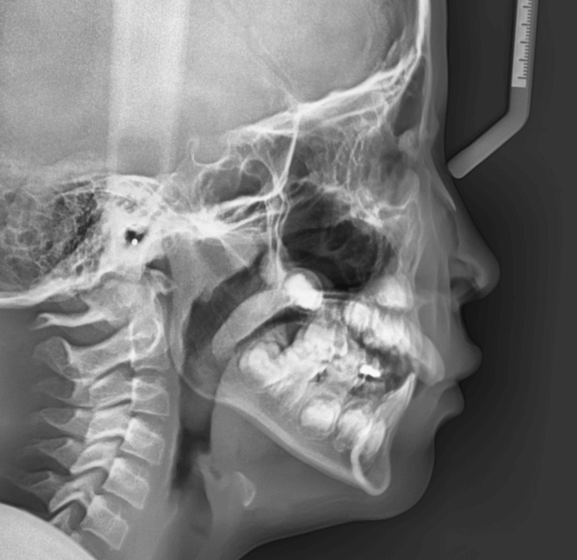

| 年齢・性別 | 8歳9ヶ月の女児 |

|---|---|

| 主訴 | 歯並びの乱れを気にされて来院された患者様です。将来的なスペース不足と歯のねじれ(翼状捻転)が懸念されました。 |

| 治療期間・回数 | 2年10ヶ月・19回 |

| 費用 | 430,000円(税別) |